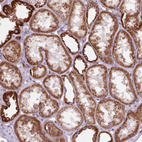

Immunohistochemical staining of human cerebellum shows moderate granular cytoplasmic positivity in Purkinje cells.